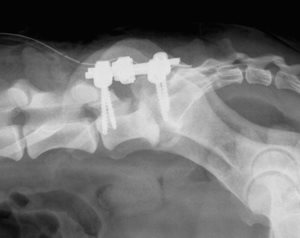

In certain cases, notably when a very large laminectomy with extension to the intervertebral joints must be performed in order to treat intervertebral foramen stenosis or, in case of the existence of a very important spondylolisthesis, a complementary stabilisation of the spine must be performed. This is carried out by the installation of pedicle screw systems and union bars or locked titanium plates. These implants block the spinal movements and allow a faster recovery by facilitating the fusion of the vertebral bodies.

Lousewort screwing by Axon Synthes system after extended L7S1 laminectomy

for herniated disc with foraminal stenosis

Lumbosacral stabilisation by pedicle screw and Unilock Synthès plates in a cat

Stabilisation of lumbosacral junction after laminectomy and bilateral foraminectomy in a cat by pedicle screws and Unilock Synthès plates